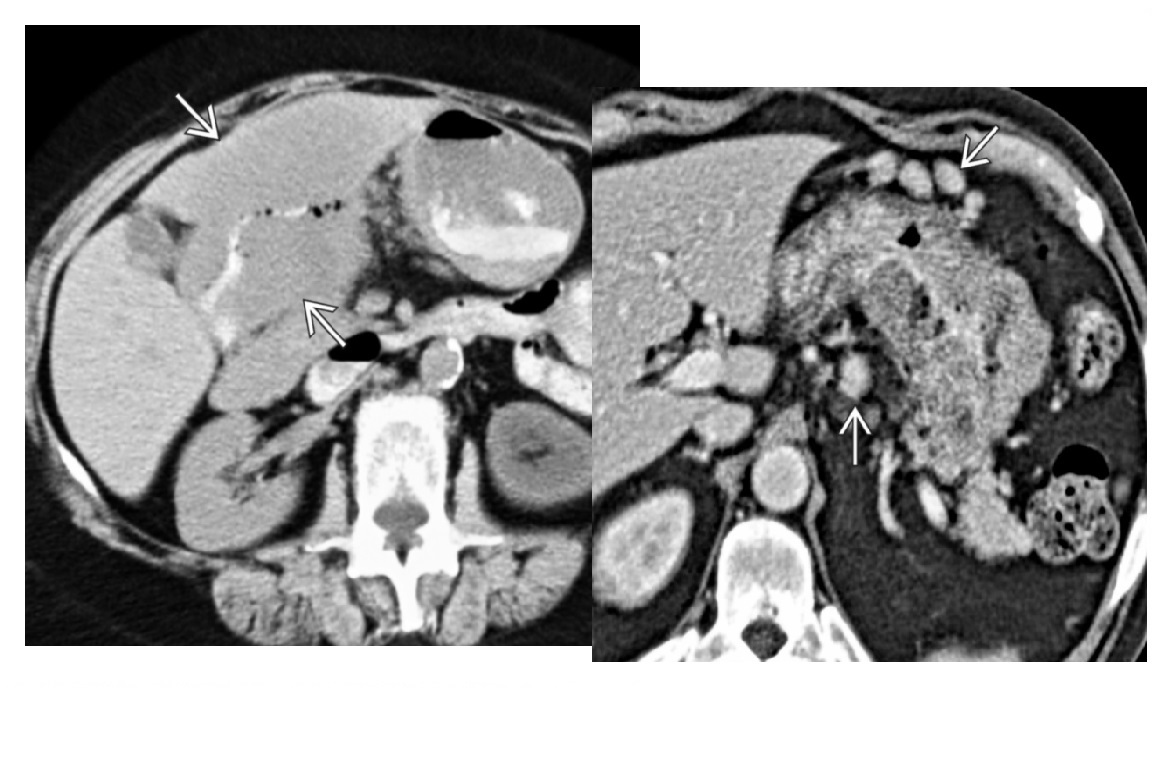

GIST

Well-circumscribed.

**Heterogenous, central necrosis is key **

Hypervascular

submucosal mass extending exophytically from GI tract

Stomach (60%) , dudoenum (30%) and oesophagus (10%)

Remember

- assocaited NF-1

- Carneys triad

- Pulmonary condromas, Exrtra-adrenal paragangliomas, GIST